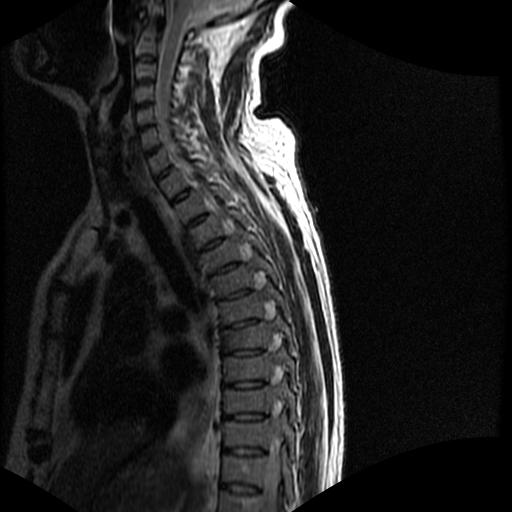

标题: MRI0985:胸椎.68岁男性,胸部疼痛,

68岁男性,胸部疼痛,不适。

t7椎体前1/3信号略减低,椎体上下面凹陷,相应脊髓几周边软组织信号未见改变。考虑:椎体退变。

胸7椎体楔状变形及信号异常,附件未见明显异常信号.椎间隙正常.未见软组织块影.考虑骨质疏松所致压缩性骨折可能大.

胸7椎体楔状变形及信号异常[t1t2 均为低信号],附件未见明显异常信号.椎间隙正常.未见软组织块影.考虑陈旧性压缩性骨折伴退变。